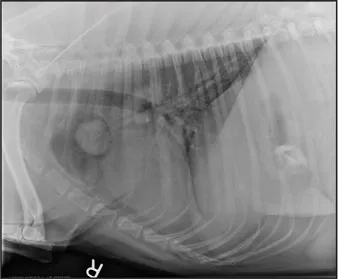

CASE 1.1 A 7-year-old neutered male Labrador Retriever who was hit by a car. You obtain these thoracic radiographs: Figs. 1.1a, b, left and right lateral projections, respectively; Figs. 1.1c, d, ventrodorsal and dorsoventral projections, respectively.

1.1b